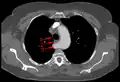

Typisches Bild einer Arteria lusoria in der Computertomographie. (1) Luftröhre, (2) Speiseröhre, dahinter (3) A. lusoria aus dem Aortenbogen entspringend.

Typisches Bild einer Arteria lusoria in der Computertomographie. (1) Luftröhre, (2) Speiseröhre, dahinter (3) A. lusoria aus dem Aortenbogen entspringend. -